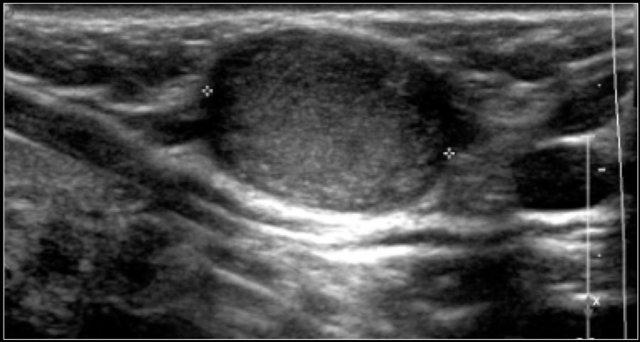

Đây là hình ảnh siêu âm của một bé gái sáu tuổi có một nang nhỏ kèm vách ngăn ở thùy tuyến giáp phải.

Nang không thay đổi trong suốt một năm.